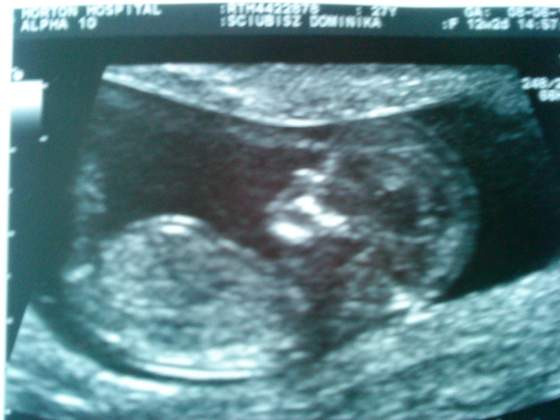

takie jakieś "surowe" to USG, czułam się bardziej jakbym była w urzędzie niż u lekarza po całej tej wizycie. Jedyne co usłyszałam od pani monitorującej to : tutaj jest serce i dzidzia wygląda zdrowa. Z karty przeczytałam, że ma prawie 53mm, przyzierność 1,5 mm, więc chyba w porządku (ale lekarska opinia dopiero po badaniu krwi), glowa wygląda normalnie(to raczej nie po mamusi

). Nawet nie powiedziała wieku (ten ze zdjęcia jest kalendarzowy), może będzie jak przyjdą wynki. Tak bardzo się cieszę.